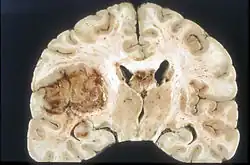

Glioma

Glioblastoma

Malignant glioma is an extremely difficult to treat brain tumor that is a leading cause of death worldwide and half of cancer-related deaths.[14] Complications associated with treating glioma include the blood brain barrier (BBB).[14] This protective mechanism for the brain also raises challenges for drug delivery through the tight junctions between endothelial cells, only allowing small lipid-soluble drugs (<400 Da) to permeate.[14] Current delivery methods are surgery and chemotherapy. SDT has been implemented as a method to open the BBB and has shown success in opening tight junctions for delivery. Examples of sonosensitizers that have shown success in glioma treatment are hematopor-phyrin monomethyl ether (HMME), porfimer sodium (Photofrin), di-sulfo-di-phthalimidomethyl phthalolcyaninezinc (ZnPcS2P2), Photolon, 5-aminolevulinic acid (5-ALA), and rose bengal (RB).[14] These have shown to induce effects such as opening of the BBB, improved vascular permeability, and apoptosis of glioma cells.